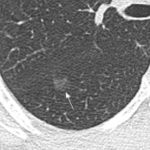

Beware of small ground-glass nodules

Small ground-glass lung nodules are common. Be careful, it might be a very invasive tumor. This article tells you more about the small signs that may draw your attention.